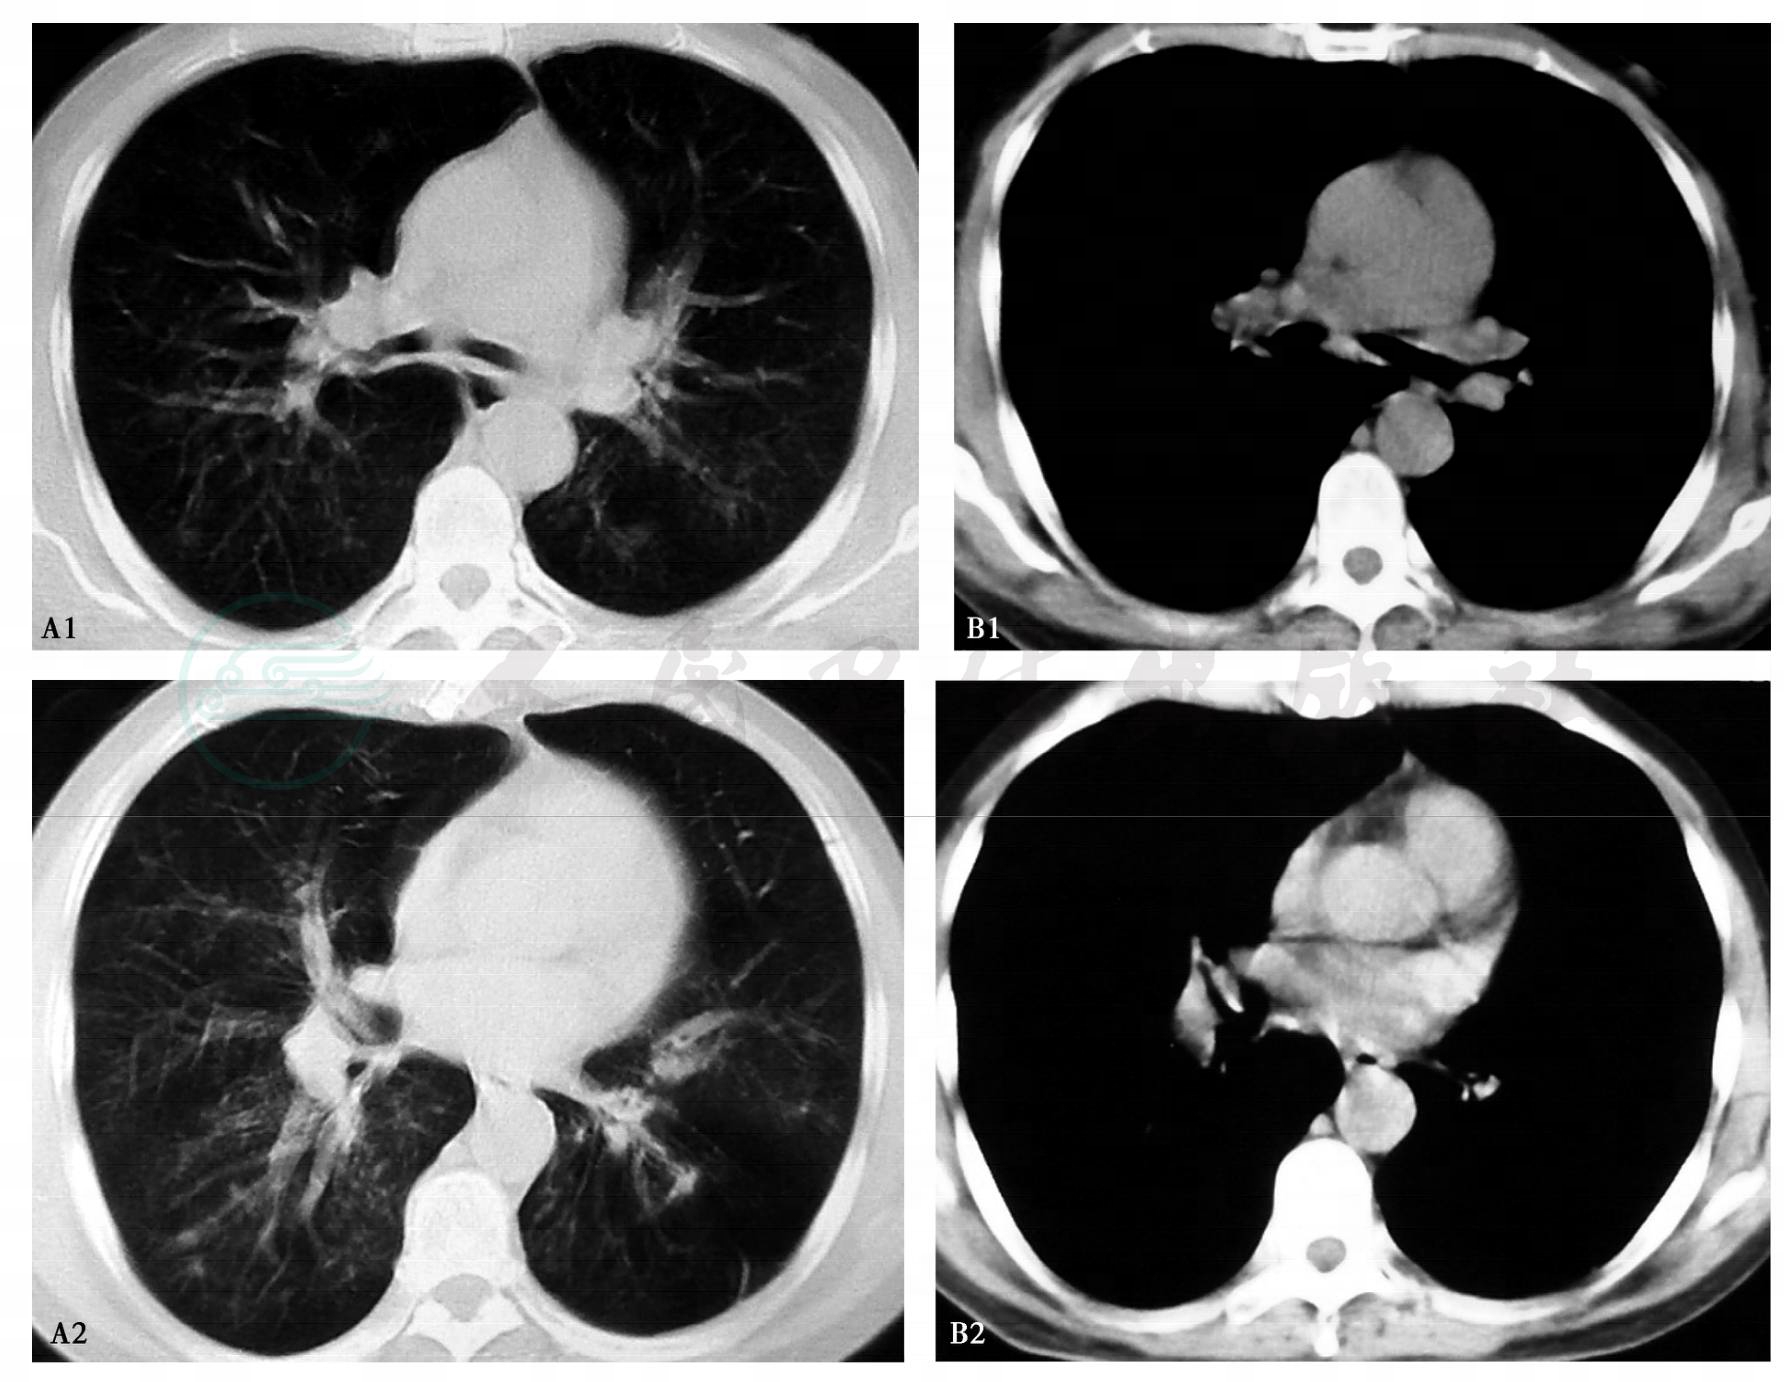

5.胸部影像学:胸部CT(2012年3月26日):双肺纹理增多紊乱,散在斑片状高密度影(图1 A肺窗,B纵隔窗)。胸部CT(2012年4月6日):双肺中心性支气管扩张,双肺散在斑片状密度增高影,部分可见空洞,左肺部分含气不均(图2 A肺窗,B纵隔窗)。

图1 胸部CT(2012年3月26日)

A肺窗,B纵隔窗

图2 胸部CT(2012年4月6日)